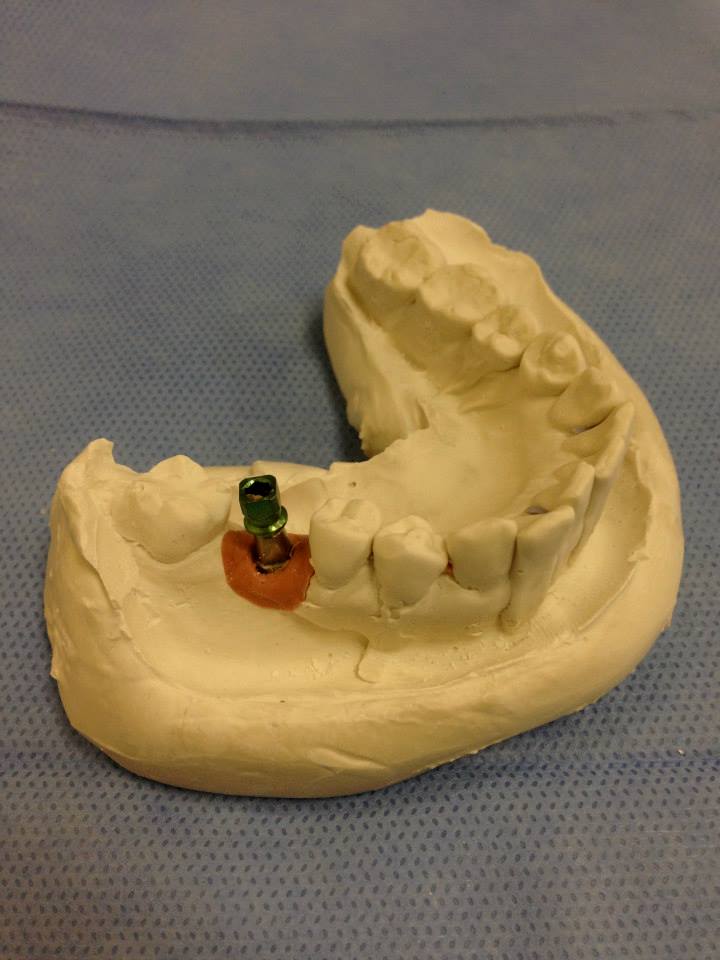

အယင္က သြားစိုက္တဲ့ဆီမွာ ရွိျပီးသားသြားကို crown စြတ္ေပးတာ၊ အံပုံတပ္ေပးတာ၊ ေဘးက သြား ၂ ေခ်ာင္းကို ပိုးျပီး ၾကားမွာ သြားအတုကို bridge လုပ္ေပးတာေတြ လုပ္ေလ့ရွိရာက ေနာက္ပိုင္းမွာ သြားကို သြားဖုံးေအာက္က အရိုး (ေမးရိုး) ထဲမွာ titanium မူလီကို ထည့္သြင္းျပီးအေပၚကေန သြားအတု စိုက္ေပးတဲ့ ေခတ္ေပၚ နည္းပညာစနစ္ကို သုံးစြဲလာၾကတယ္လို႔ ဆိုပါတယ္။

ေမးရိုးထဲမွာ တိုင္ေတနီယံသံေခ်ာင္းကို ထည့္သြင္းျခင္း၊ လူရဲ့ အရိုးမ်ားက အဆိုပါပစၥည္းကို လက္ခံသည့္ တုန္႔ျပန္႔မႈေကာင္းျခင္း၊ ၎အေပၚက သြားတုကို တပ္ဆင္ျပီးေနာက္ သြားတု၏ တုန္႔ျပန္မႈ၊ ထိေတြ႔မႈတို႔မွာ လူနာအတြက္ အေႏွာက္အယွက္မျဖစ္ျခင္းတို႔ေၾကာင့္ ရိုးရိုးသြားတုမ်ား တပ္ဆင္တာထက္ ယခု DENTAL IMPLANT က သြားစိုက္သူမ်ားအတြက္ သင့္ေတာ္တဲ့ ေရြးခ်ယ္မႈ ျဖစ္လာတယ္လို႔ ဆိုပါတယ္။

အဆိုပါ DENTAL IMPLANT နည္းပညာနဲ႔ စနစ္ကို ေဒါက္တာေမာင္ေမာင္ေသာ္က သီးျခား သင္တန္းမ်ား တက္ေရာက္ျပီး စာေတြ႔ လက္ေတြ႔ တတ္ေျမာက္ေအာင္ သင္ၾကားရယူခဲ့တယ္လို႔ သိရပါတယ္။ ယခုအခ်ိန္မွာ သူ႔ေဆးခန္းမွာ အဆိုပါ နည္းပညာနဲ႔ သြားစိုက္ေပးျခင္းကို ေအာင္ျမင္စြာ ေဆာင္ရြက္ေနျပီလို႔ ဆိုပါတယ္။ သြားစိုက္ရန္မလိုတဲ့ လူနာေတြအတြက္ မူလသြားအေဟာင္းကို ျပဳျပင္ျပီး အေပၚက သြားအတု စြတ္ေပးတဲ့ CROWN လုပ္ေပးတဲ့ အလုပ္ကိုလည္း ေဆးခန္းမွာ စက္ကိရိယာမ်ား ၀ယ္ယူထားျပီး ခ်က္ျခင္း စက္နဲ႔ လုပ္ေပးႏိုင္တယ္လို႔ သူက ေျပာျပပါတယ္။